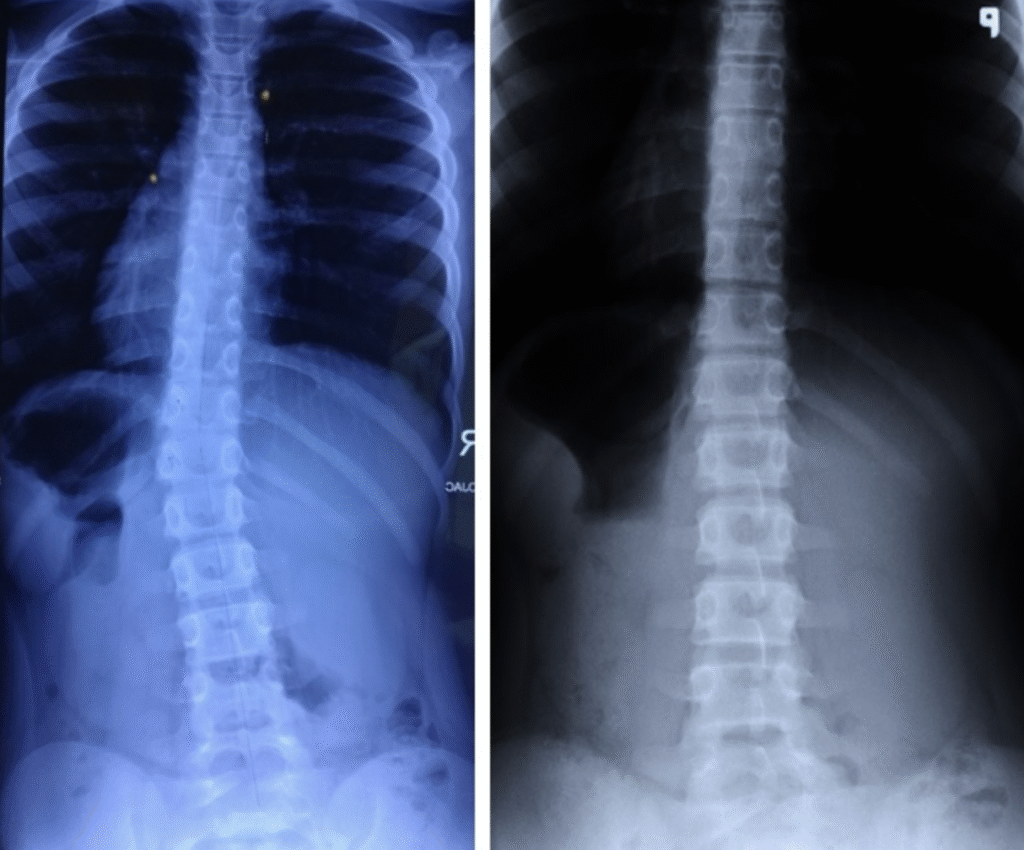

Martyna – 10 lat

Terapia prowadzona w okresie 03.10.2016 – 02.01.2017 (20 zabiegów) Częstotliwość zajęć – 2 x tydz. Po skończonej terapii dziecko było pod kontrolą naszego ośrodka. W lutym 2019 zrobiono zdjęcie RTG, które nie wykazało skrzywienia kręgosłupa.